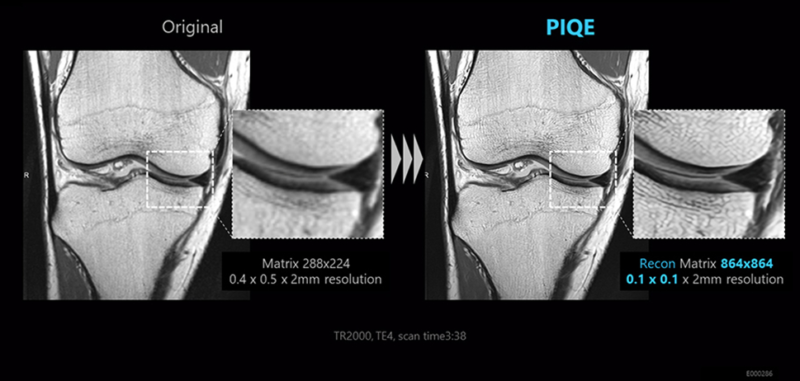

Vantage Galan 3T/Focus Edition tạo ra hình ảnh độ nét cao và thăm khám tiêu chuẩn trong thời gian ngắn bằng cách cài đặt công nghệ cải tiến SNR và công nghệ hình ảnh tốc độ cao được thiết kế bằng cách sử dụng Deep Learning.

• Tín hiệu số hóa sắc nét cung cấp SNR tăng 20% thông qua Công nghệ PURERF và Saturn